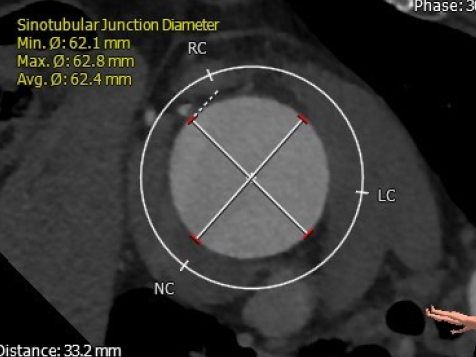

窦管交界处直径:62.4mm